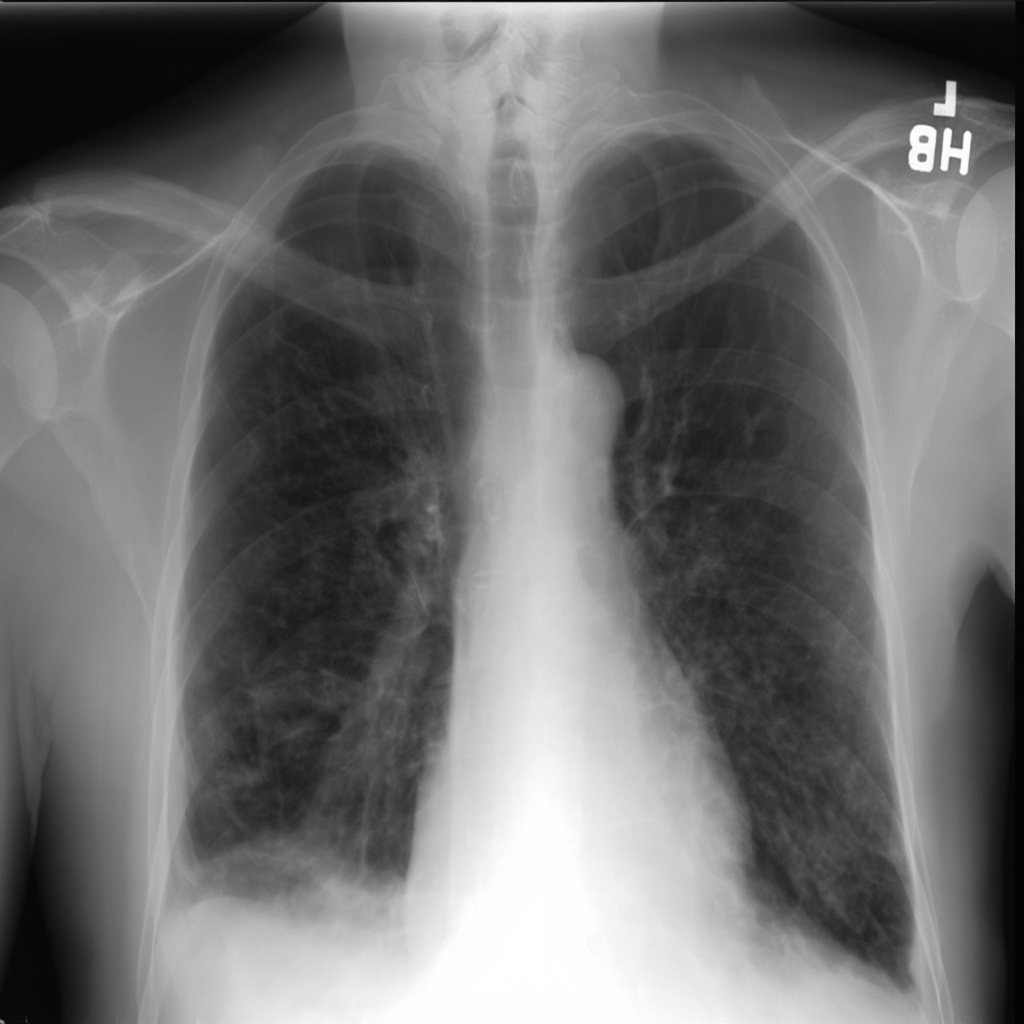

Chest X-ray

Chest X-ray (CXR)